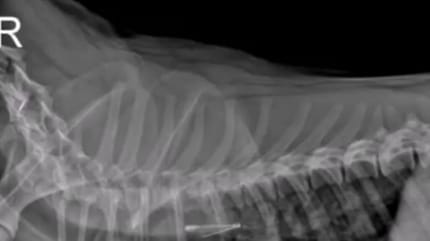

Parę dni temu Trójmiejska Klinika Weterynaryjna opublikowała na swoim profilu na Facebooku filmik, na którym można podejrzeć pracę lekarzy. Na nagraniu widać fragment zabiegu endoskopowego usunięcia otwartej agrafki z przełyku psa.

Jak sami weterynarze przyznają: połknięcie agrafki jest łatwiejsze niż jej wyciągnięcie, dlatego wszyscy oglądaliśmy nagranie z zapartym tchem.

Na szczęście lekarzowi Piotrowi Pankowi i asystentce Kaśce Wrońskiej udało się pomóc zwierzakowi. Piesek wrócił do domu jeszcze tego samego dnia.